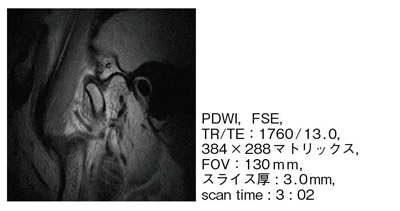

【顎関節マイクロコイル画像】